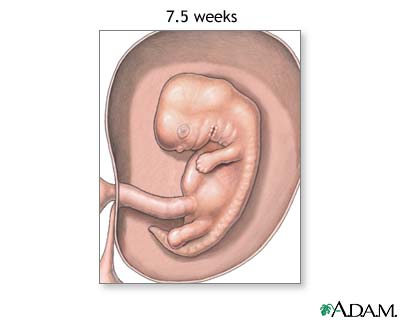

Week 8

- Your baby's arms and legs have grown longer.

- Hands and feet begin to form and look like little paddles.

- Your baby's brain continues to grow.

- The lungs start to form.

Week 9

- Nipples and hair follicles form.

- Arms grow and elbows develop.

- Your baby's toes can be seen.

- All of your baby's essential organs have begun to grow.